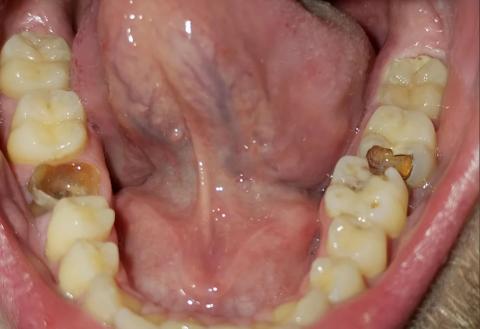

The image shows the lower jaw (mandible) with multiple back molars affected by visible decay. On both the left and right sides, at least one molar shows brown cavitated lesions, indicating advanced tooth decay. The surrounding gum tissue appears slightly irritated, and the floor of the mouth is clearly visible.

This pattern suggests bilateral molar decay, which increases the overall infection risk.

Multiple decayed lower molars

Deep dental caries reaching dentin

High risk of tooth abscess formation

Possible early pulp infection

Risk of periodontal involvement around molars

Professional Comment